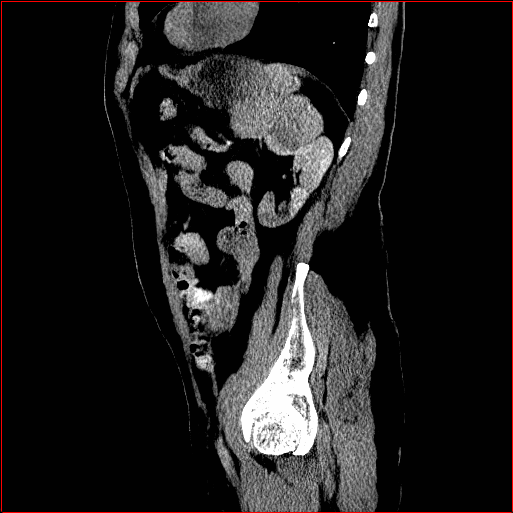

Abdomen Region

1×1×0.71\times 1\times 0.7

mm

512×512×768512\times 512\times 768

Figure 3: MAISI-v2 segmentation-guided results for small to large volume size and three different regions.